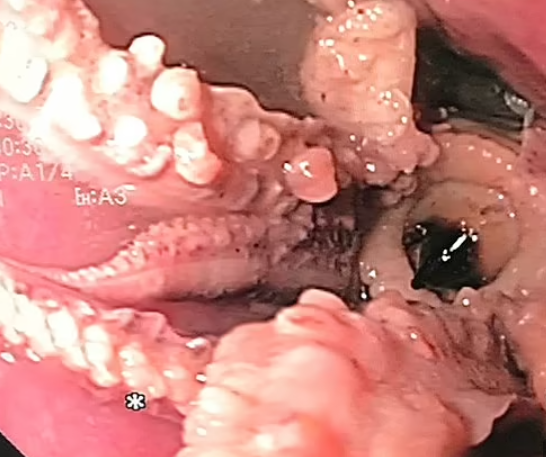

Astfel, ei au făcut o descoperire bizară: bărbatul avea o caracatiță întreagă, blocată la cinci centimetri de joncțiunea dintre esofag şi stomac.

Descoperirea șocantă făcută de medici în esofagul unui pacient / Sursa foto: Clinical Gastroenterology and Hepatology

Inițial, medicii au încercat să extragă sau să împingă caracatița care nu-i permitea bărbatului să respire corespunzător, relatează Daily Mail.

În cele din urmă, medicii au folosit forcepsul pentru a extrage capul caracatiței. Pacientul și-a revenit rapid după procedură și a fost externat două zile mai târziu.